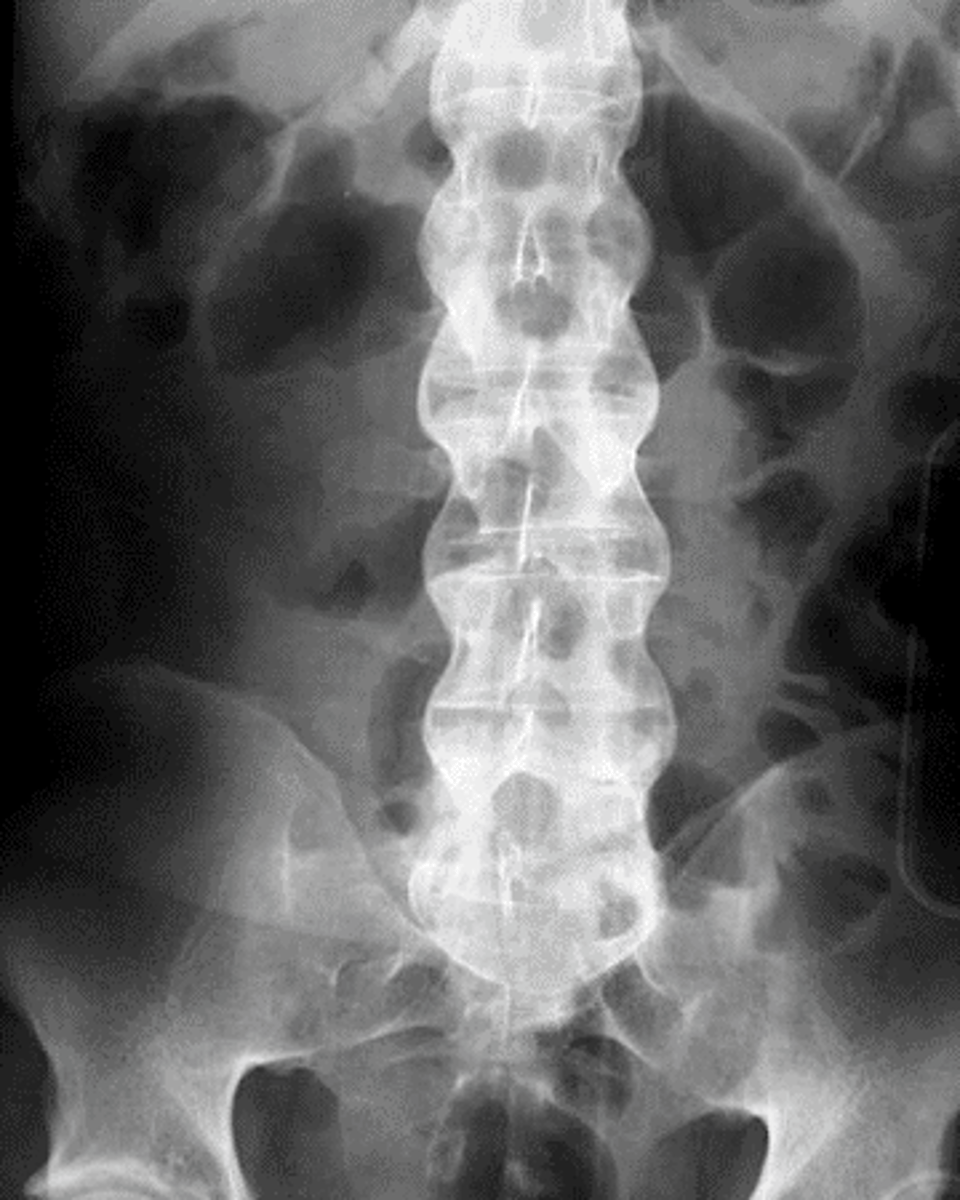

ankylosing spondylitis

form of spinal arthritis

*ages 25-45 years of age

CHARACTERISTICS:

1. bamboo spine

- starts to fuse

2. decreases lordosis, decreases flexibility

3. restricted chest expansion

4. increased thoracic kyphosis